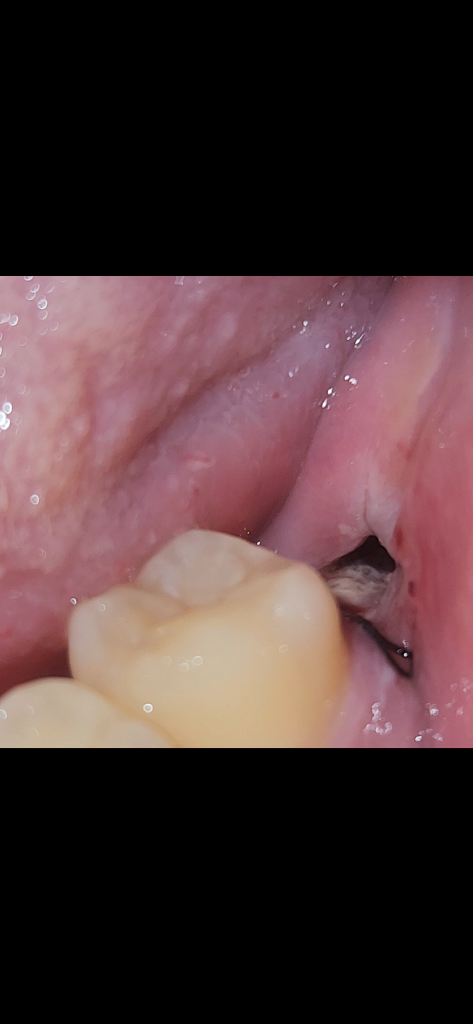

사진상에 보이는건 음식물도 잇고 상처가 치유되는과정중에 생기는 현상이니 너무 걱정하지 않으셔도 됩니다.

사진상으로는 특별한것은 안보입니다.

가글해보시고 안되면 그냥 그대로 두시면 될 것 같습니다